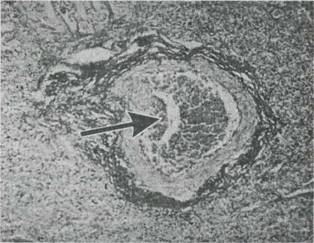

Fig. 9-29. Persistenta hipertensiunii pulmonare la un nou nascut. Sectiune histologica prin pulmon. Conform clasificarii Heath-Edwards a modificarilor vasculare , pulmonare, preparatul evktentiaza o leziune n stadiul III, cu modificari ocluzive. Media arteriala este mult ngrosata, cantitate crescuta de tesut fibro-elastic n peretele vascular (col.Van Gieson); lumenul arterial este partial obstruat.